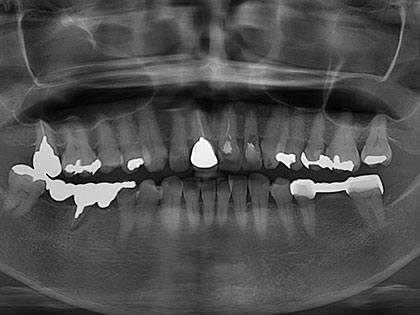

• インプラント術前1

• インプラント術前2

• 治療中の写真がこちら

• インプラント治療中1

• インプラント治療中2